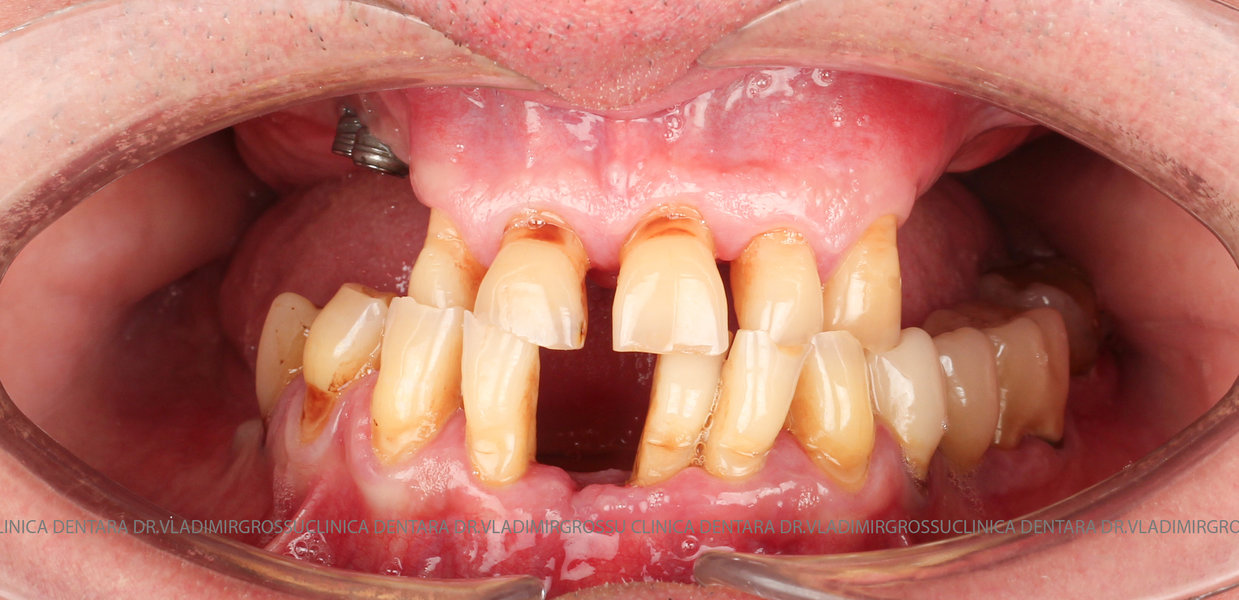

Cazuri clinice conceptul All-on-6